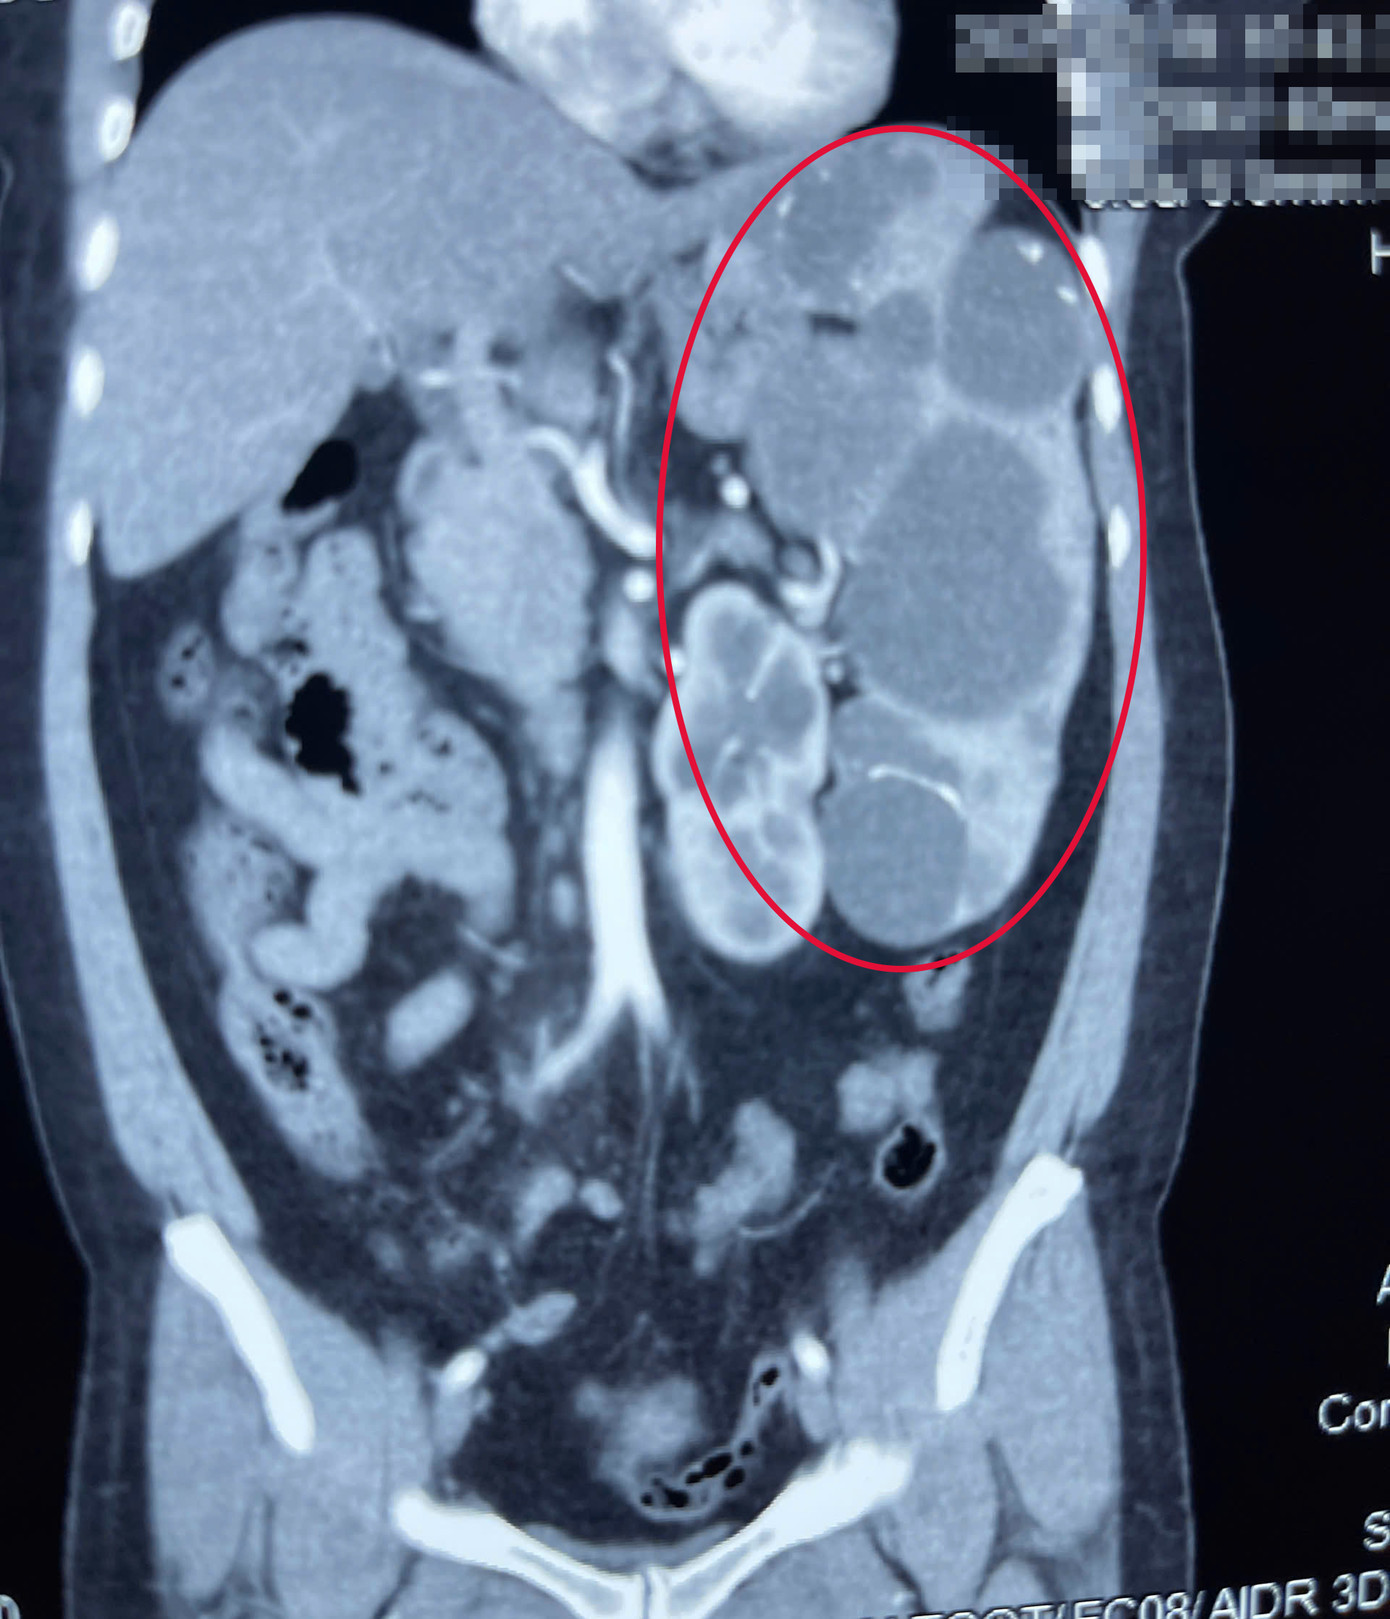

| Khối lách phát triển rất lớn chiếm diện tích ổ bụng, chèn ép các bộ phận nội tạng của người bệnh |

Thời gian gần đây, triệu chứng đau bụng ở người bệnh xuất hiện thường xuyên, ảnh hưởng nghiêm trọng đến chất lượng sống. Khi đến bệnh viện thăm khám, qua chẩn đoán hình ảnh, bác sĩ phát hiện người bệnh có lách to bất thường, chiếm gần hết vùng bụng bên trái. Lá lách của người bệnh có nhiều nang lớn.